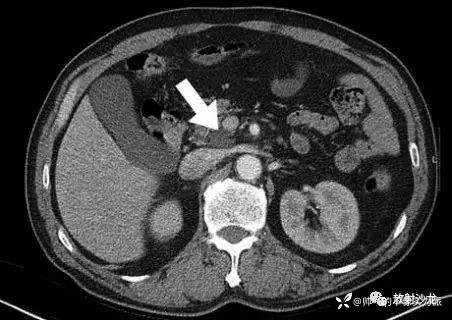

胸部平片见图1。胸部CT扫描显示多发结节、双侧气腔实变和磨玻璃征(图2),多发结节都分布在淋巴组织周围。腹部CT平扫显示胰头处有一个直径2 cm 的低密度团块阴影(图3)。对患者行气管镜检查以除外恶性疾病或结核,术中未见支气管内病变。对支气管镜获取的样本进行了细胞学检测、抗酸染色和TB聚合酶链反应,结果均为阴性;支气管肺泡灌洗液培养也为阴性。多重聚合酶联反应未检测到A 型和B 型流感病毒、1~3型副流感病毒、呼吸道合胞病毒、腺病毒、鼻病毒以及间质肺病毒。

图3 腹部CT示胰头有一直径2 cm 的低密度团块阴影(箭头处)